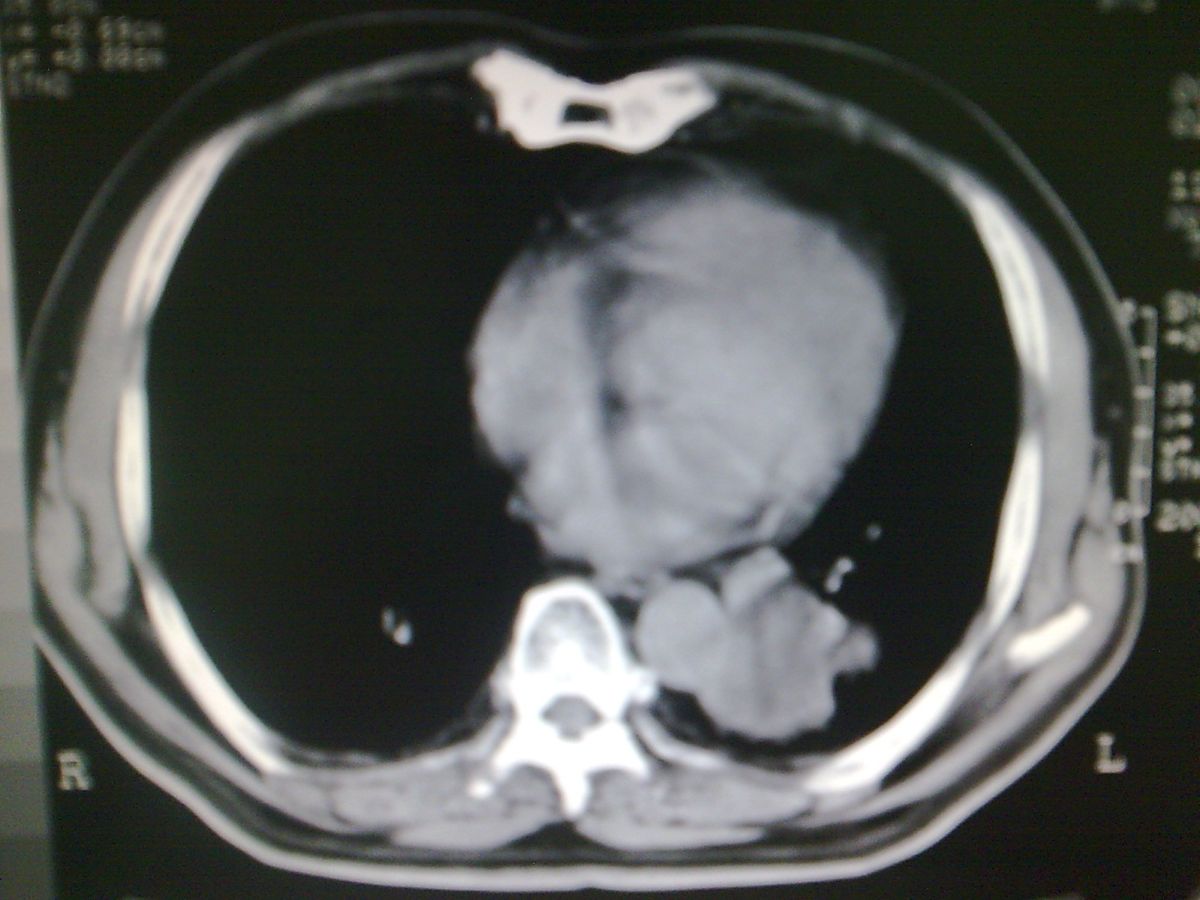

标题: CT19282:男性,70岁,咳血, [打印本页]

标题: CT19282:男性,70岁,咳血,

图片少了些,考虑周围性肺癌

考虑周围性肺癌

周围型肺癌。

考虑左下肺周围性肺癌。

考虑左下周围型肺癌可能性大。

考虑左肺下叶周围型肺癌可能。